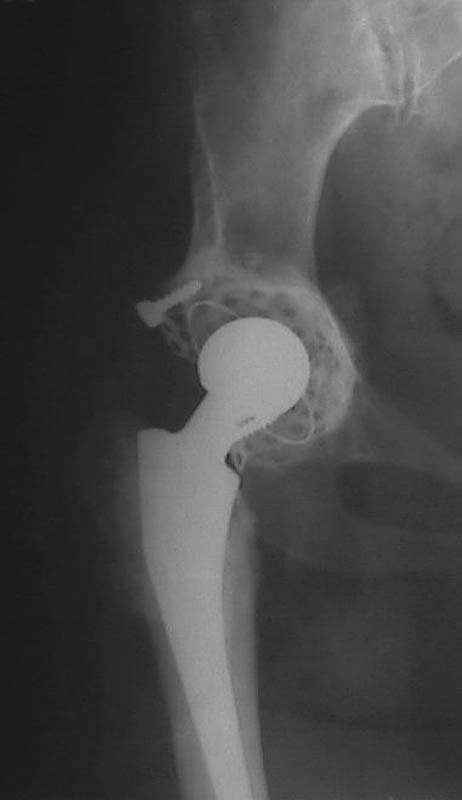

Вывих чашки

Мужчина, 38 лет. Двусторонний диспластический коксартрз, кифосколиоз.Правый сустав прооперирован 12.12.00, левый - в апреле 2003 г. Справа вывихнулась <чашка>.

Предполагается заменить <чашку>, наростив крышу <тутопластом>? Возможно ли использовать бесцементную <чашку>? Мнения? Заранее благодарю! С уважением,А.В.Владзимирский

На мой взгляд, оптимальным вариантом может быть использование антипротрузионой сетки и цементной чашки. Пластика крыши с учётом величины дефекта - любым материалом на Ваше усмотрение (ауто-, алло-)

Использовать бесцементную чашку я бы не рискнула.